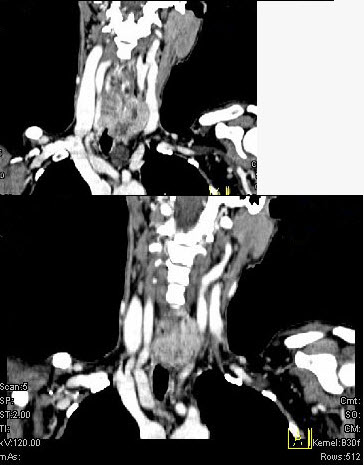

女,50岁,左下颈部扪及一质硬、表面高低不平的包块,肿块逐渐增大,现感吞咽困难,CT如图所示,最可能诊断为()。

A、甲状腺癌

B、食管癌

C、喉癌

D、甲状腺原发淋巴瘤

E、颈部神经鞘瘤

A